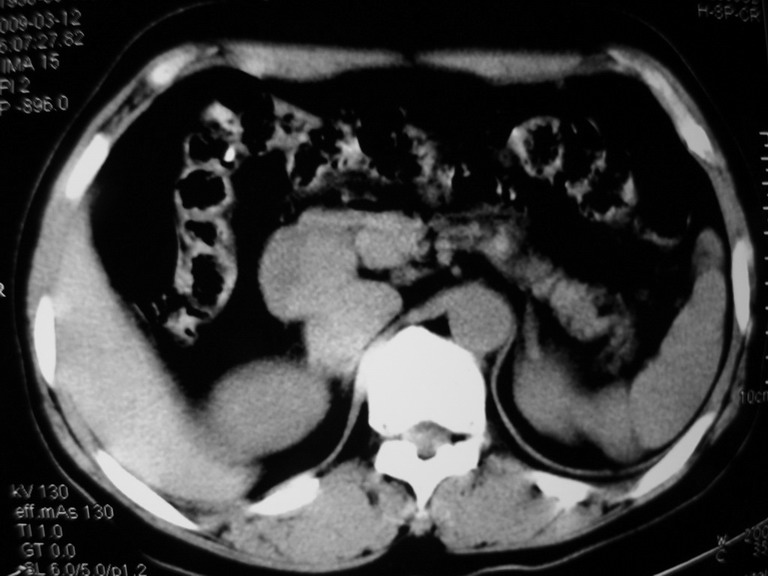

接着往下一贴看,有静脉期和延迟期,在看看和下腔静脉及十二指肠的关系,腔静脉内是不是栓子?

考虑肝右叶与尾叶交界区肝癌(部分外生),侵犯下腔静脉并下腔静脉瘤栓形成。